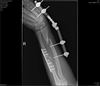

Bud rad, zes nedopad treba takhle…

jo zápěstí jsou parádní, potom co jsem obě zrakvil, tak se vyhýbám koloběžce :-D První se zhojila celkem dobře (14dní jsem s tou zlomeninou chodil do práce potom 3 tejdny sádra) a chvíli jsem zase mohl skákat přes kaluže. Driuhá zlomenina byla horší, podélně jsem si rozštípnul vřetenní kost a ruka občas bolí ještě dneska (asi 2 roky). Nicméně naštěstí žádnej podobnej tuning…